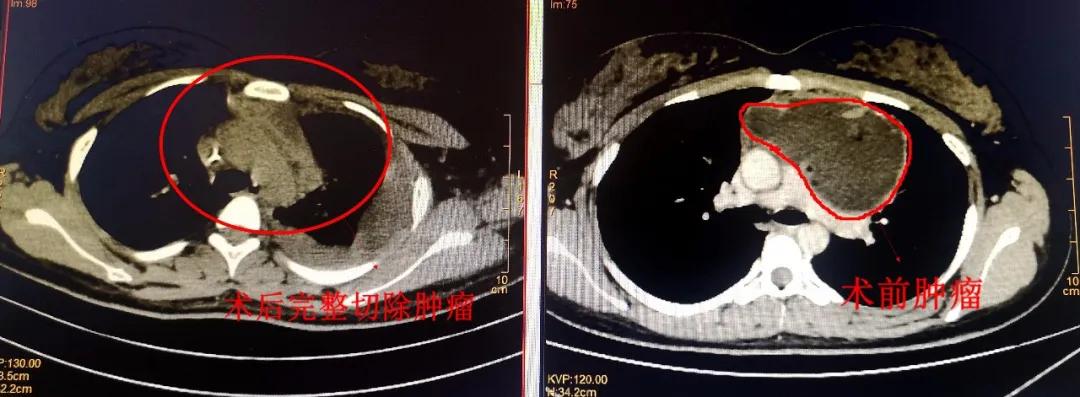

术后胸部留下疤痕的困扰让他们对手术一直犹豫不决,就在小黄母亲左右为难时,亲戚告知漳州市第三医院叶惠龙院长在胸部疾病治疗有丰富的临床经验,可通过胸腔镜微创技术将纵膈肿瘤经腋窝下取出,做到术后伤口的完美“隐藏”。抱着一丝希望,他们慕名来到了漳州市第三医院胸外科,找到叶惠龙院长,经过详细询问病情并完善检查后,CT结果显示:“前纵膈占位”,肿瘤大小约7*10*6cm,必须尽快进行手术治疗!

在与小黄家属充分沟通后,由叶院长主刀,在科主任邱晖、林锦荣主治医师、麻醉科及手术室全力配合下,为患者行“单孔胸腔镜下经左胸入路前纵膈肿瘤切除术”,由于前纵膈血管多,且患者肿瘤大,临近心脏及主动脉血管,手术难度极大,对主刀医师的技术有很高的要求,手术团队克服重重困难,历经1个多小时手术顺利完成,术中出血不到10ml。由于该类微创手术只需在腋下开一个小口,既能完整切除肿瘤,缓解症状,又能让切口更加美观,手术损伤小,术后疼痛更轻。患者也能得到较快恢复,不到一周时间,小黄便顺利出院了。